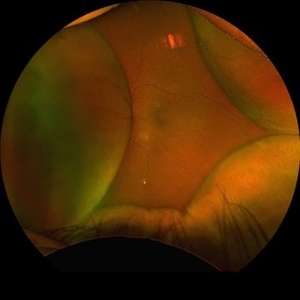

Giant Retinal Tear with Choroidal Detachment

Giant Retinal Tear with Choroidal Detachment

Jun 12 2024 by Anand Temkar

Intra operative still of a 34 year old male showing Giant Retinal Tear with Choroidal Detachment.

Photographer: Dr.Anand Temkar- Retina Foundation, Ahmedabad

Condition/keywords: choroidal detachment, giant retinal tear